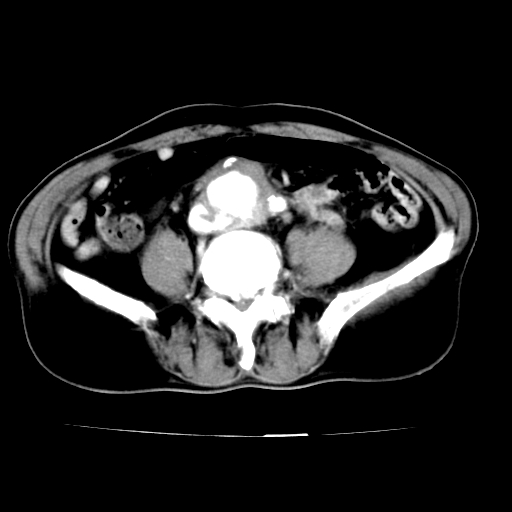

男,75岁,腹痛月余,彩超发现脐周腹主动脉异常回声。临床诊断:腹主动脉瘤。

ct诊断:右骼总动脉囊性动脉瘤并瘤内附壁血栓形成,与下腔静脉之间形成动静脉瘘。

腹主动脉分叉处真性动脉瘤,附壁血栓形成。

给平扫片看看血管壁钙化情况。

此病例平扫图像已发,请大家看看!